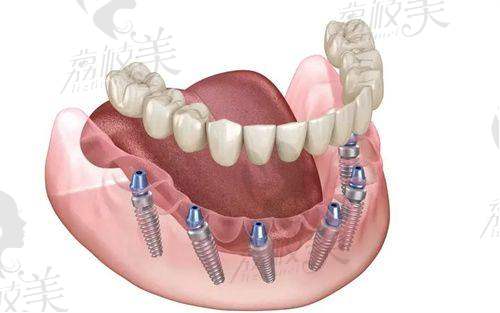

硬核设备:引入瑞士Straumann种植系统、数字种植导航系统(拍一张CT图,术前就能看到种好牙后的成效图),机器指导植入路线,连菜鸟医生都能稳准种牙。